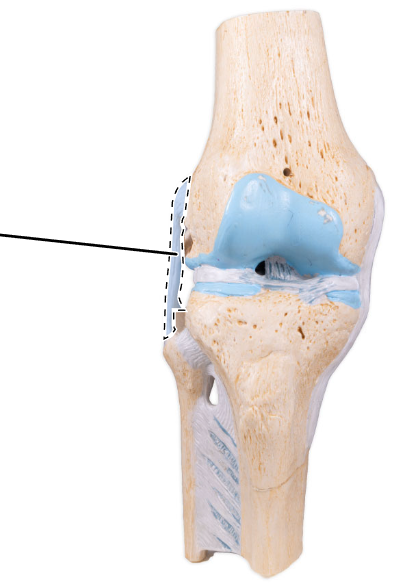

What is the joint shown here?

The tibiofemoral joint.

What is the joint shown here?

The tibiofemoral joint.

What ligament is shown here?

Patellar ligament.

What ligament is shown here?

Lateral (fibular) collateral ligament.

What ligament is shown here?

Lateral (fibular) collateral ligament.

What ligament is shown here?

Medial (tibial) collateral ligament.

What ligament is shown here?

Medial (tibial) collateral ligament.

What is the highlighted fibrocartilage?

Lateral meniscus.

What is the highlighted fibrocartilage?

Lateral meniscus.

What is the highlighted fibrocartilage?

Medial meniscus.

What is the highlighted fibrocartilage?

Medial meniscus.